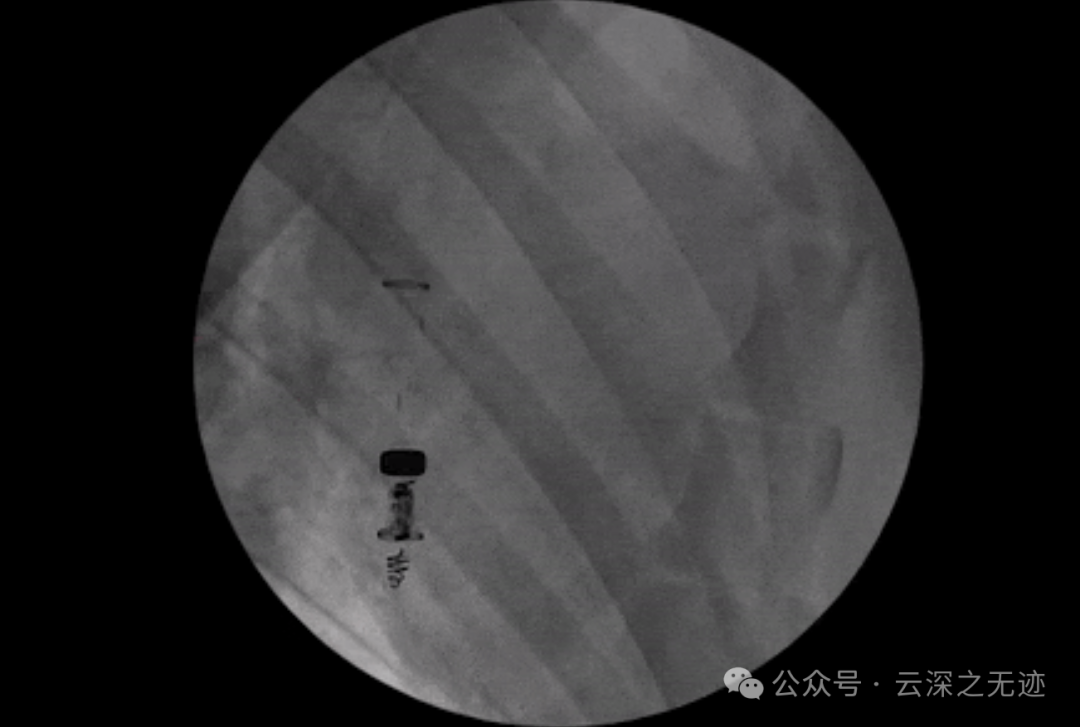

X光的照片

右心室(RV)装置示意图,用于将生物机械能从心脏运动转换为电能并调节心律失常,该装置由能量收集单元(EHU)、电源管理单元和起搏器模块(PMU&PM)、钩子和不透射线标记。

黑色的地方有些放射性物质来引导X光